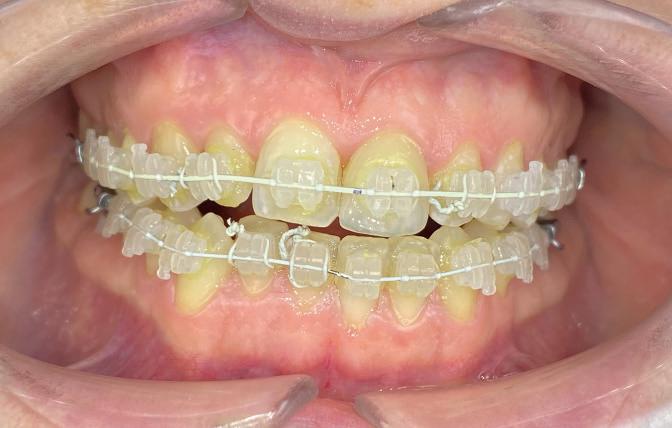

Timothy Zoltie is Head of the Medical & Dental Illustration Department, based within the School of Dentistry at the University of Leeds, in a collaborative role with Leeds Teaching Hospitals NHS Trust. He is an award-winning professional photographer and videographer, in the speciality area of medicine and dentistry. A Fellow of the Institute of Medical Illustrators, as well as a Fellow of the Royal Photographic Society, Timothy Zoltie also works as Editor in Chief of the Journal of Visual Communication in Medicine.

The School of Dentistry at the University of Leeds stands as a preeminent hub for dental education and research, distinguished by its expert faculty and state-of-the-art training facilities. Renowned as a leading centre for dental study, the school is committed to shaping the future of dentistry by nurturing the skills of the next generation of dental professionals. A unique element of the institution is that it has a dedicated Dental Photography Department, one of only a few in the world. The dental photography department at the University of Leeds has been delivering high-quality dental photography services for over 60 years, and currently photographs over 8,000 patients per year.

In reviewing the market for camera systems to use for dental and clinical photography, Timothy was looking for a compact solution that would capture the highest-quality images, while offering versatility to shoot stills and video.

solution and results

After reviewing the various options, Timothy chose the Sony Alpha a7R V Mirrorless camera system. In capturing stills and video, the camera provides the versatility Timothy was looking for in his hybrid role, where he not only photographs clinical conditions but also undertakes clinical videography. The seamless interchangeability of lenses for video and stills on a single system significantly enhances workflow efficiency. The compact form factor of Sony cameras improves manoeuvrability and user comfort, which is particularly advantageous for repetitive tasks such as intra-oral photography. Manual focusing for Timothy is crucial in dental

photography for maintaining consistent working distances and is facilitated by the Sony 90mm Macro G OSS lens. It is the only mirrorless lens in its focal range equipped with lens distance scales and ratios on the barrel.

“The Sony FE 90mm Macro G is one of the sharpest macro lenses I have used, Timothy explains. “Clarity is imperative when undertaking clinical photography and paired with a high-resolution camera such as the Sony Alpha 1 or Sony Alpha a7R V, it allows exceptional documentation of clinical detail.”

When Timothy is shooting in clinical conditions, where stopped-down apertures of f/22 are used for increased depth of field, effective lighting is crucial. Flash is the key source of illumination and the Godox MF-R76S+ Ring Flash developed jointly with Sony Europe is used with the Sony Alpha camera. This dedicated dental kit is easy to set up and delivers the required picture quality in combination. The optimised dental kit compatibility for Sony Alpha cameras provide highly accurate E-TTL functionality that produces the correct exposure on every shot, regardless of camera-tosubject distance.

Another camera feature Timothy uses is custom modes. This enables standardised settings for specific tasks, streamlining workflows and minimising errors. For example, custom mode 1 can be assigned for intraoral photography, and custom mode 2 can be designated

t imothy recommends that other dental professionals considering using sony alpha cameras should test the kits that fit their practice, explore the system’s versatility, and invest in dental photography training.

He said: “take time to understand the camera’s features and functionalities to unlock the full potential of the camera, such as how to calibrate and set up custom modes, and how to switch between them. Once calibrated, the sony system paired with the dedicated Godox MF-R76s+ for sony alpha cameras is by far one of the easiest camera set ups for dental photography and can be used by any of the dental team.”

for videography, with all the associated settings for each mode saved.

The adoption of Sony Alpha cameras at the University of Leeds has significantly elevated the quality and efficiency of dental photography and videography. Timothy Zoltie’s experience highlights the importance of a versatile and user-friendly camera system in the specialised field of dental imaging.

Timothy said: “Choosing a hybrid system has proven very advantageous, seamlessly facilitating the interchangeability of lenses for

both video and stills. This versatility enables me to effortlessly transition between filming surgical procedures and undertaking commercial healthcare photography commissions for marketing agencies or NHS institutions.

“The Sony Alpha cameras’ hybrid functionality, complemented by features such as manual focusing and custom modes, makes them ideally suited to dental photography and they have become indispensable assets for documenting clinical procedures and conditions at the School of Dentistry.” n www.masteringdentalphotography.com